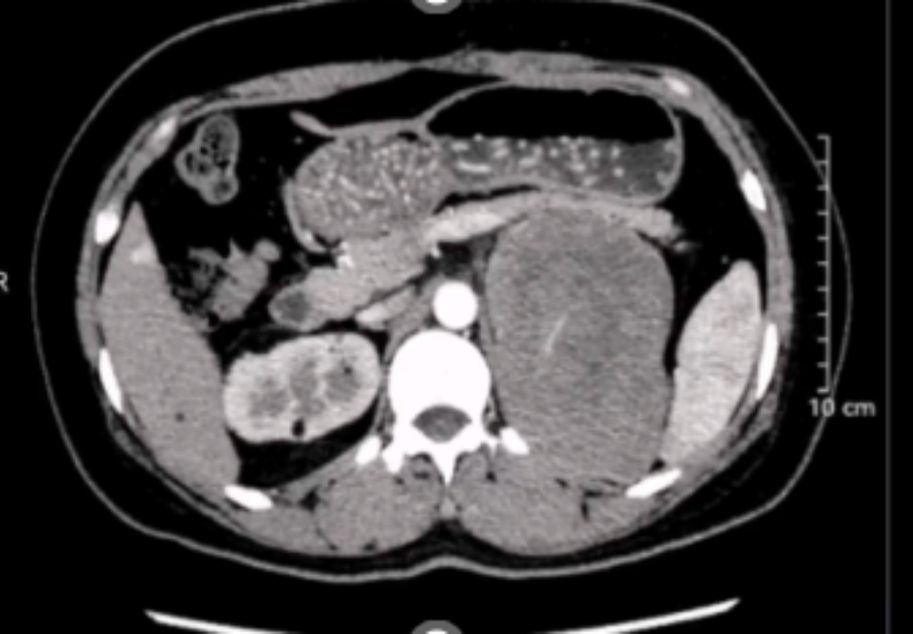

患者女性,34岁,因左肾肿瘤行左肾切除术,术后1年发现局部复发伴肺部转移。患者于2022年6月,因左肾血管平滑肌脂肪瘤在外院接受左肾切除术,2023年7月患者复查发现左侧腹膜后占位,2023-07-21外院超声造影:1.左肾切除术后;2.左侧腹膜后低回声团块,呈“不均匀性增强”(MT可能性大),2023-07-21外院肺部CT:双肺新增多发结节影,考虑转移瘤。2023-07-24在外院行超声引导下左侧腹腔肿物粗针穿刺活检术,病理回报:腹膜后淋巴结送检标本镜下见上皮样血管平滑肌脂肪瘤伴坏死,请结合临床。免疫组化结果: HMB45、MelanA阳性,Desmin少量阳性,CK-pan、CD10、Ihibin-a 阴性。目前诊断:1.左侧腹膜后上皮样血管平滑肌脂肪瘤;2.左肾切除术后。此次会诊的目的:下一步治疗方案?手术?化疗?靶向治疗?

影像科周秀秀主治医师:患者腹部CT影像显示:左侧腹膜后血管平滑肌脂肪瘤,肿瘤体积较大,直径达10cm以上,病灶中央可见坏死灶,同时肺部CT显示双肺新增多发结节影,考虑为转移瘤,提示该肿瘤进展较快,结合病理报告,考虑属于特殊类型的血管平滑肌脂肪瘤。

泌尿外科任吉忠教授:患者1年前接受手术治疗切除肾脏肿瘤,术后病理诊断为罕见的上皮样血管平滑肌脂肪瘤,术后仅1年左右,肿瘤再次复发,并生长至10cm以上,提示该肿瘤恶性度高、进展快,且存在加速进展的可能。目前除了口服依维莫司治疗,可以考虑手术切除复发肿瘤,同时对肺转移灶进行穿刺活检,可以利用切除的肿瘤组织和穿刺组织进行基因检测,寻找潜在的敏感靶点,同时注意密切监测随访患者全身情况。